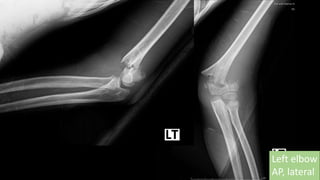

Left elbow AP, lateral

จากรพช.

Left elbow

AP, lateral

Totally displacement

Closed fracture of left supracondyle

Gartland III

Left elbow AP,lateral จากรพช.